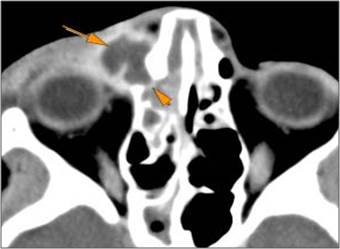

The preseptal soft tissues including the lacrimal gland and sac are abnormal.

There is evidence of a subperiosteal hematoma along the medial or lateral wall, roof or floor of the orbit.

The circumferential extraconal and the intraconal orbital fat are infiltrated.

There is evidence of herniated intra-orbital fat.